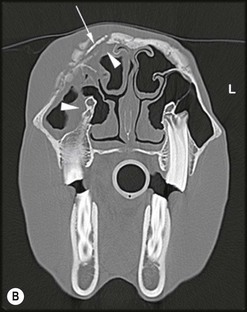

Fig. 13.43 Radiograph (A) and CT images (B and C) of a compound odontoma in a 2-year-old TB colt.

(Images courtesy of J. Easley.)